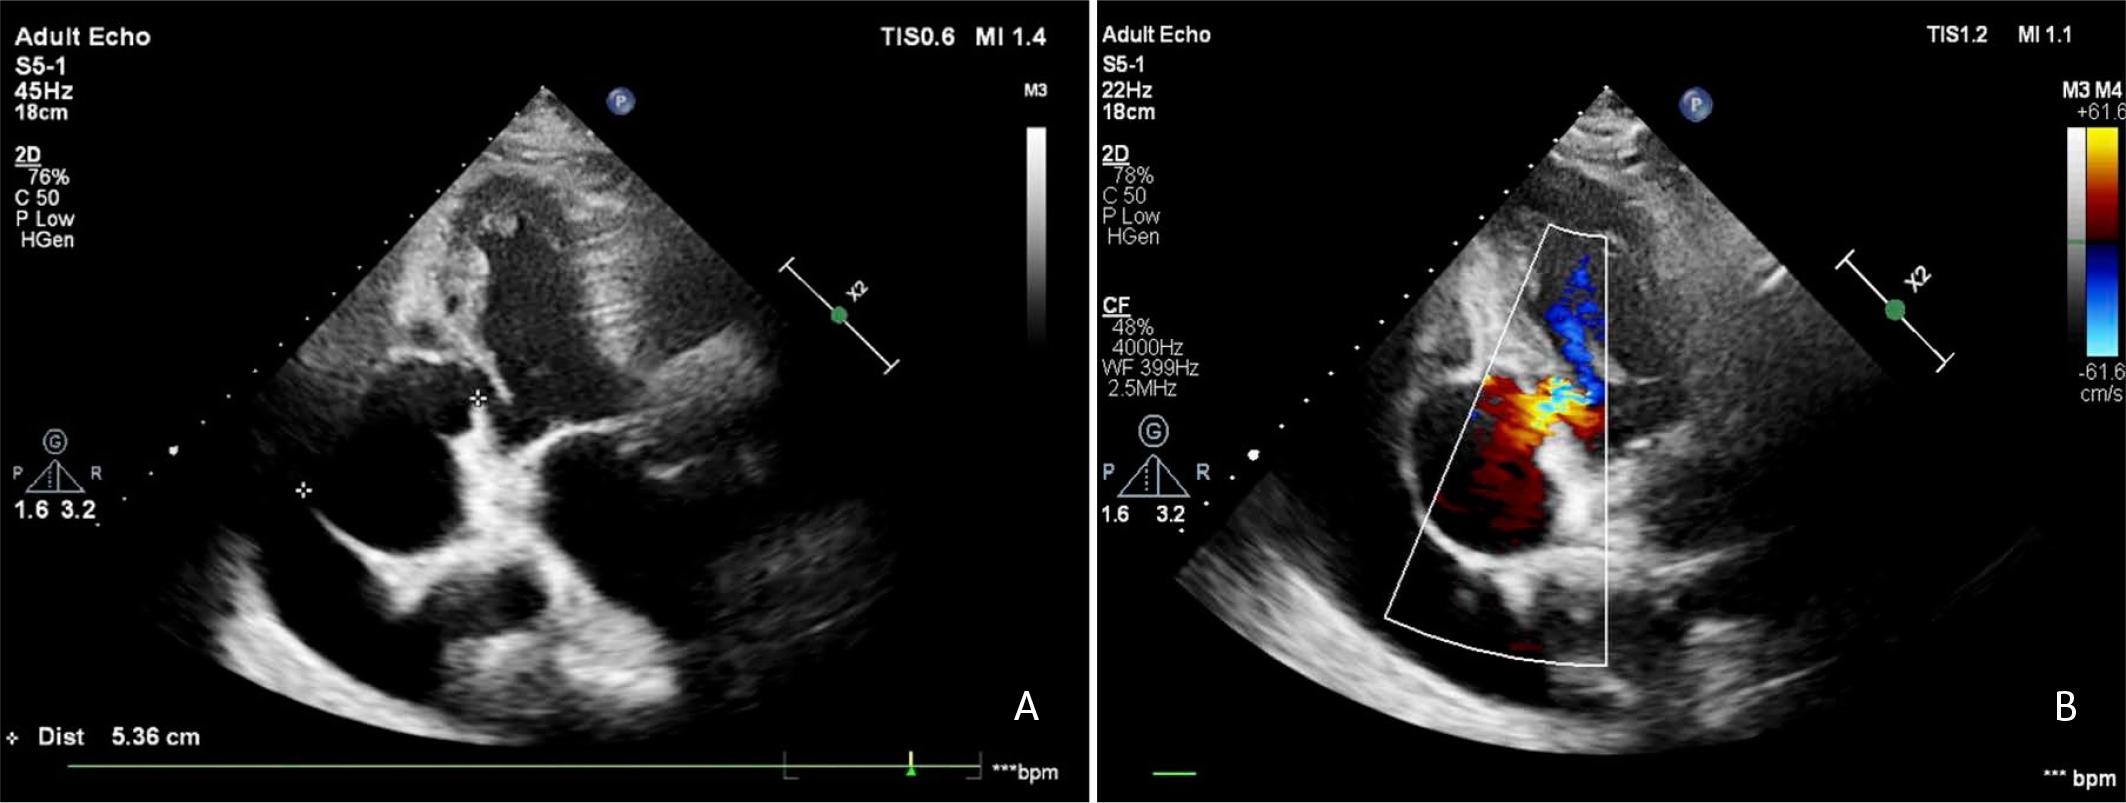

FIGURE 1.